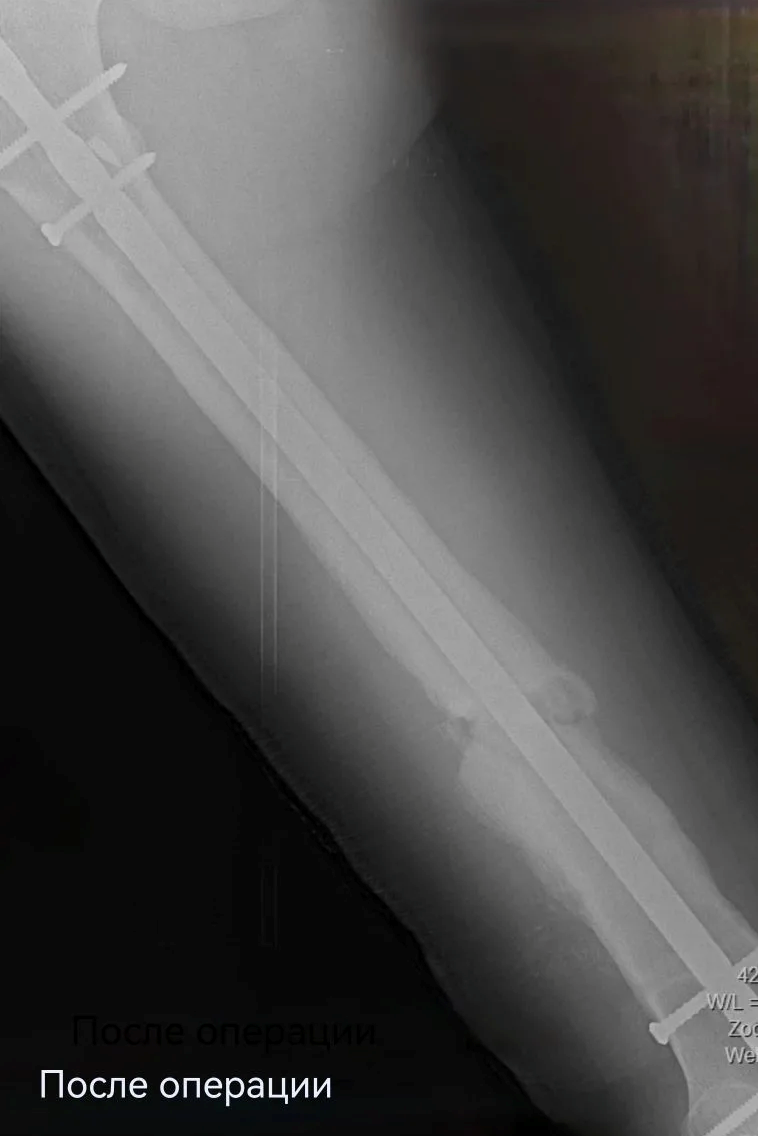

После успешного удаления прежней конструкции пациенту установили новую надежную систему - с учётом предыдущего опыта. Для этого понадобилось несколько небольших разрезов (не более 2 см). На второй день после операции Николай передвигался по отделению с помощью костылей, уже нагружая оперированную конечность. Сейчас он внимательнее прислушивается к рекомендациям, от выполнения которых зависит благополучие восстановительного периода.

Этот клинический пример подчёркивает ключевую особенность работы травматологов‑ортопедов: умение выходить за рамки стандартных протоколов, когда этого требует ситуация. Профессионализм команды — в способности анализировать, комбинировать методики и конструировать новые технические решения в процессе подготовки к операции. В результате несовершеннолетний пациент получил лечение, максимально учитывающее его индивидуальные особенности и текущее состояние, а также приступил к реабилитации в раннем послеоперационном периоде.